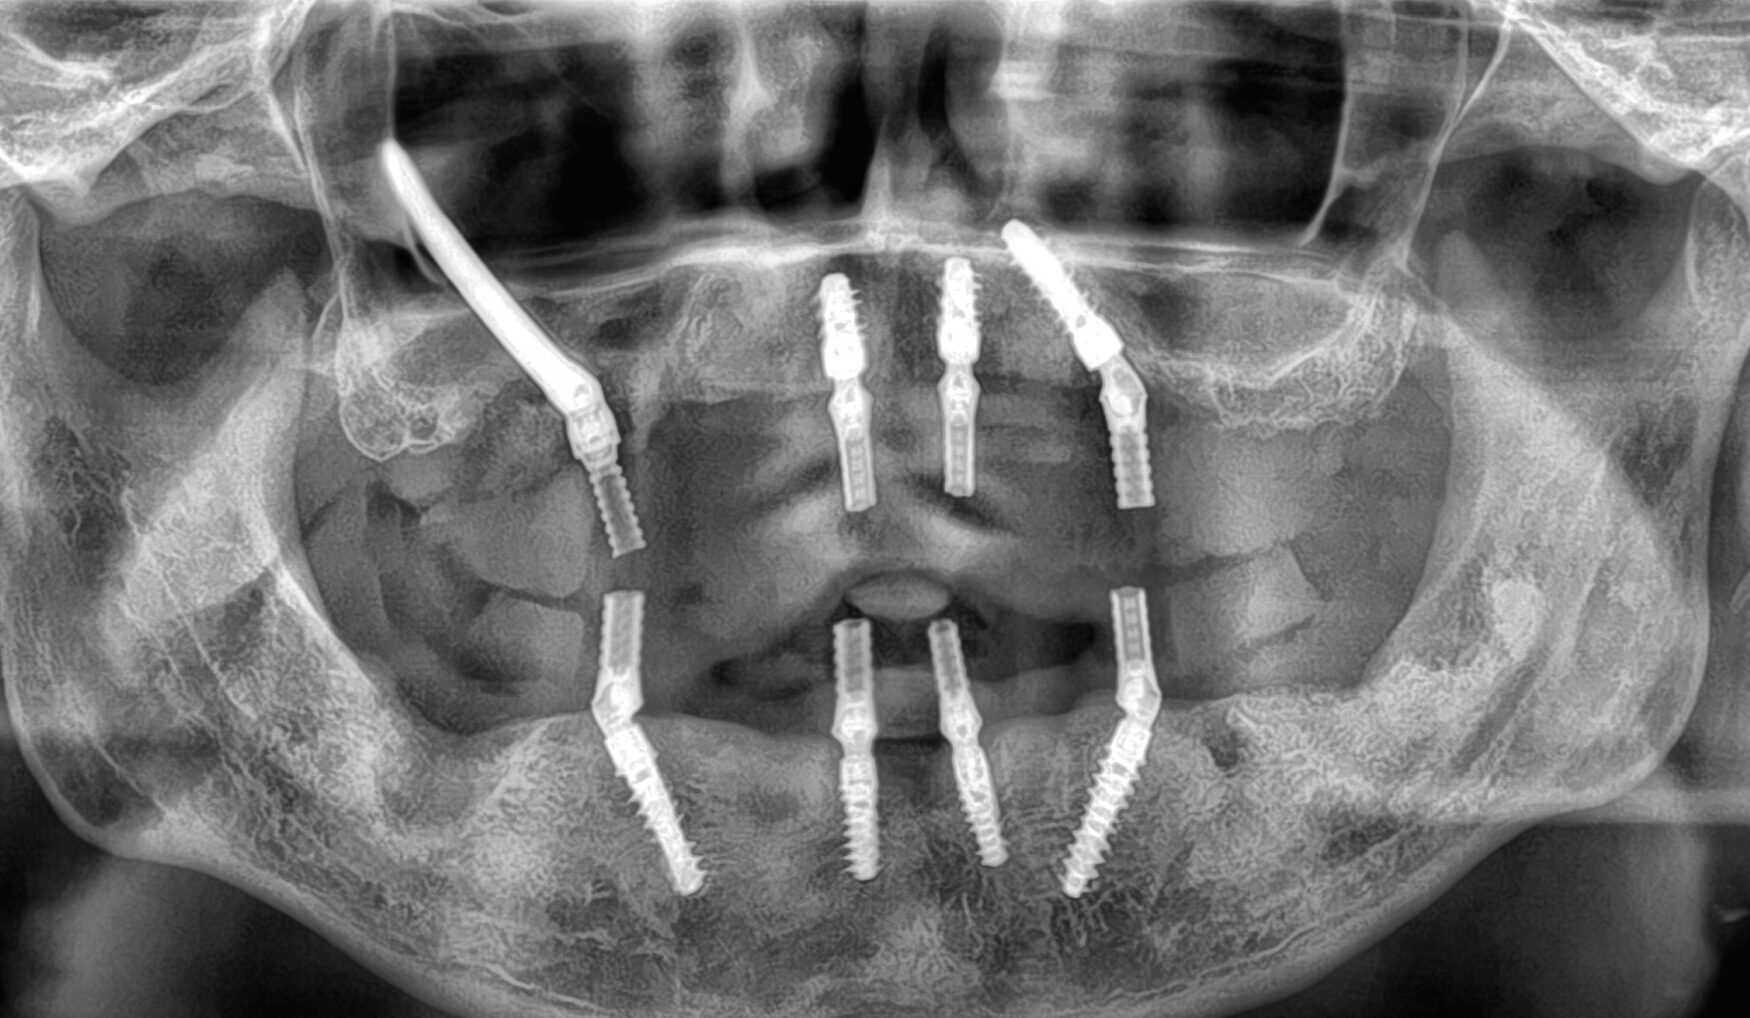

CASE

1